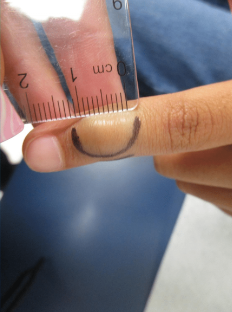

The plexiform fibrohistiocytic tumor, first described in 1988, is primarily found in children and young adults, with a notable female predominance (80%). These tumors typically present as solitary, slow-growing subcutaneous nodules, most commonly on the upper extremities (65%) or lower extremities (27%). While generally slow-growing, they may exhibit low-grade malignant behavior and have the potential for local recurrence after surgical excision; however, metastasis to lymph nodes or lungs is rare.

In the presented case, the patient had a chronic, asymptomatic nodule. The punch biopsy findings revealed nodular collections of histiocytes with foamy cytoplasm within a fibrotic stroma, suggesting a diagnosis of xanthogranuloma or a related histiocytic process. The presence of a rare multinucleated histiocyte supports this interpretation. Negative immunostains for S100, EMA, and CK8/18 rule out conditions like melanoma and certain epithelial tumors, while a negative Fite stain indicates no mycobacterial infections. However, given the depth of involvement, the pathologist was unable to exclude a plexiform fibrohistiocytic tumor.